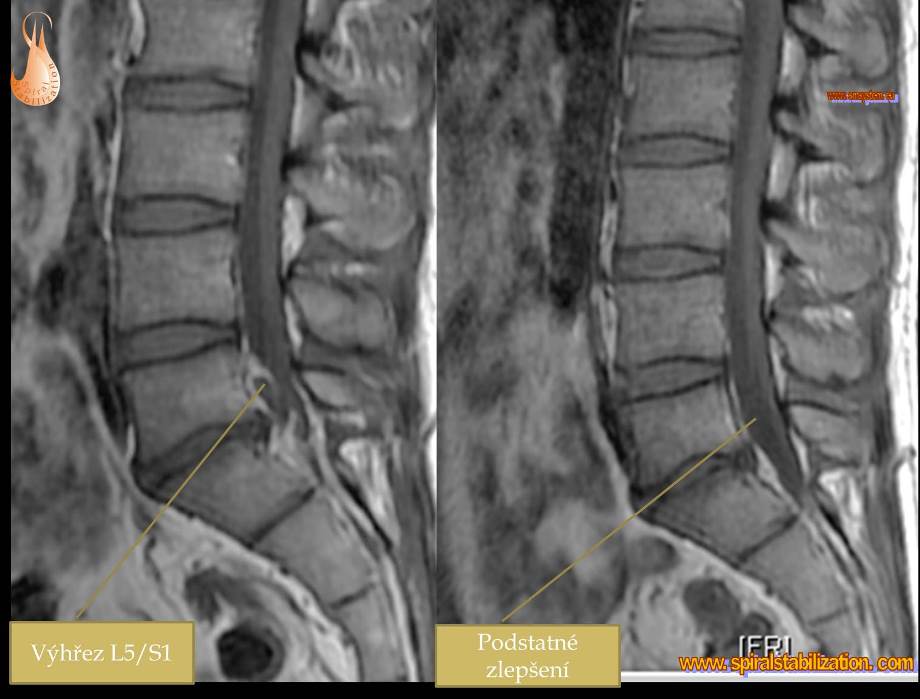

Výsledky hernia L5/S1